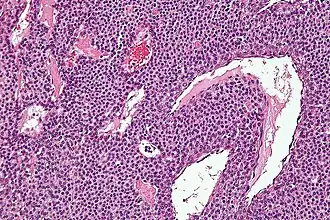

Гломусная опухоль уха (гломангиома) — преимущественно доброкачественное новообразование, развивающееся из клеток параганглиев, ассоциированных с симпатическими и парасимпатическими ганглиями, привязанными к таким анатомическим образованиям как аурикулярная ветвь блуждающего нерва (нерв Арнольда), барабанный нерв (ветвь языкоглоточного нерва, нерв Якобсона), луковица яремной вены.

Наиболее адекватным считается термин параганглиома, так как он соответствует понятию о гистологическом строении данной опухоли и подразумевает общность патогенеза с гомологичными новообразованиями другой локализации, так же развивающихся из параганглионарной ткани — параганглиомами лёгких, кожи, надпочечников (феохромоцитома). Параганглиомы латерального основания черепа ассоциированы с парасимпатическими ганглиями в обилии представленными в этой анатомической зоне.